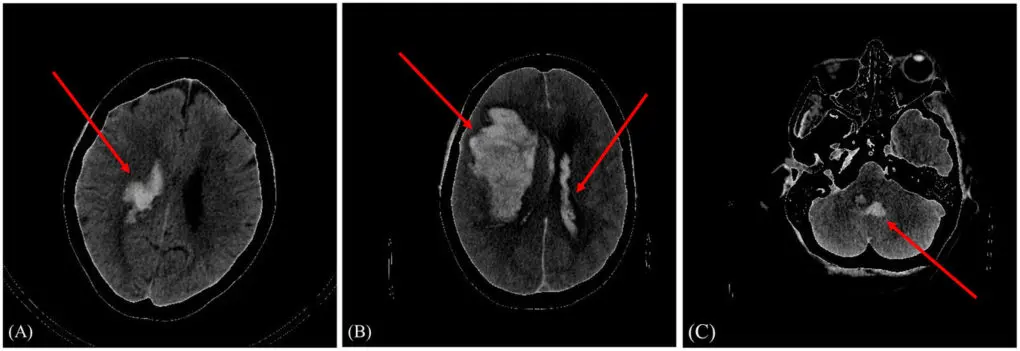

Un modelo que es capaz de predecir el pronóstico, favorable o no, de un paciente tras sufrir una hemorragia intracraneal. Es uno de los resultados de la tesis doctoral de Amaia Pérez del Barrio, médico radióloga del Hospital Universitario de Navarra, durante su residencia en el Hospital Universitario Marqués de Valdecilla (HUMV), y codirigida por Lara Lloret, investigadora del Grupo de Computación Avanzada del Instituto de Física de Cantabria (IFCA, CSIC-UC) y el doctor de la Universidad de Oviedo, José Antonio Vega.

Hasta ahora existían varios modelos de predicción para la detección de la hemorragia cerebral. Lo novedoso en este caso es que se presenta un modelo de aprendizaje profundo que predice el pronóstico de la enfermedad, es decir, si el paciente evolucionará favorablemente o no.

“Incluimos en el estudio a 262 pacientes de Cantabria que llegaban al servicio de urgencias de Valdecilla con sospechas de hemorragia intracraneal y con las imágenes de los distintos TAC cerebrales y sus datos clínicos, entrenamos un modelo personalizado para poder clasificar a los pacientes en mal pronóstico y buen pronóstico, utilizando un modelo híbrido”, explica la radióloga.

Este modelo se conoce como híbrido porque incluye dos grupos de datos: las imágenes del TAC y datos de cada paciente, y, por tanto, el rendimiento de la red mejora, “a más datos, mejores predicciones”, afirma Pérez. Esos datos se obtienen de información personal como, por ejemplo, la edad, sexo, si el paciente es fumador o consumidor de alcohol habitual, antecedentes médicos, hipertensión, diabetes, colesterol, y parámetros de la analítica de sangre realizada.